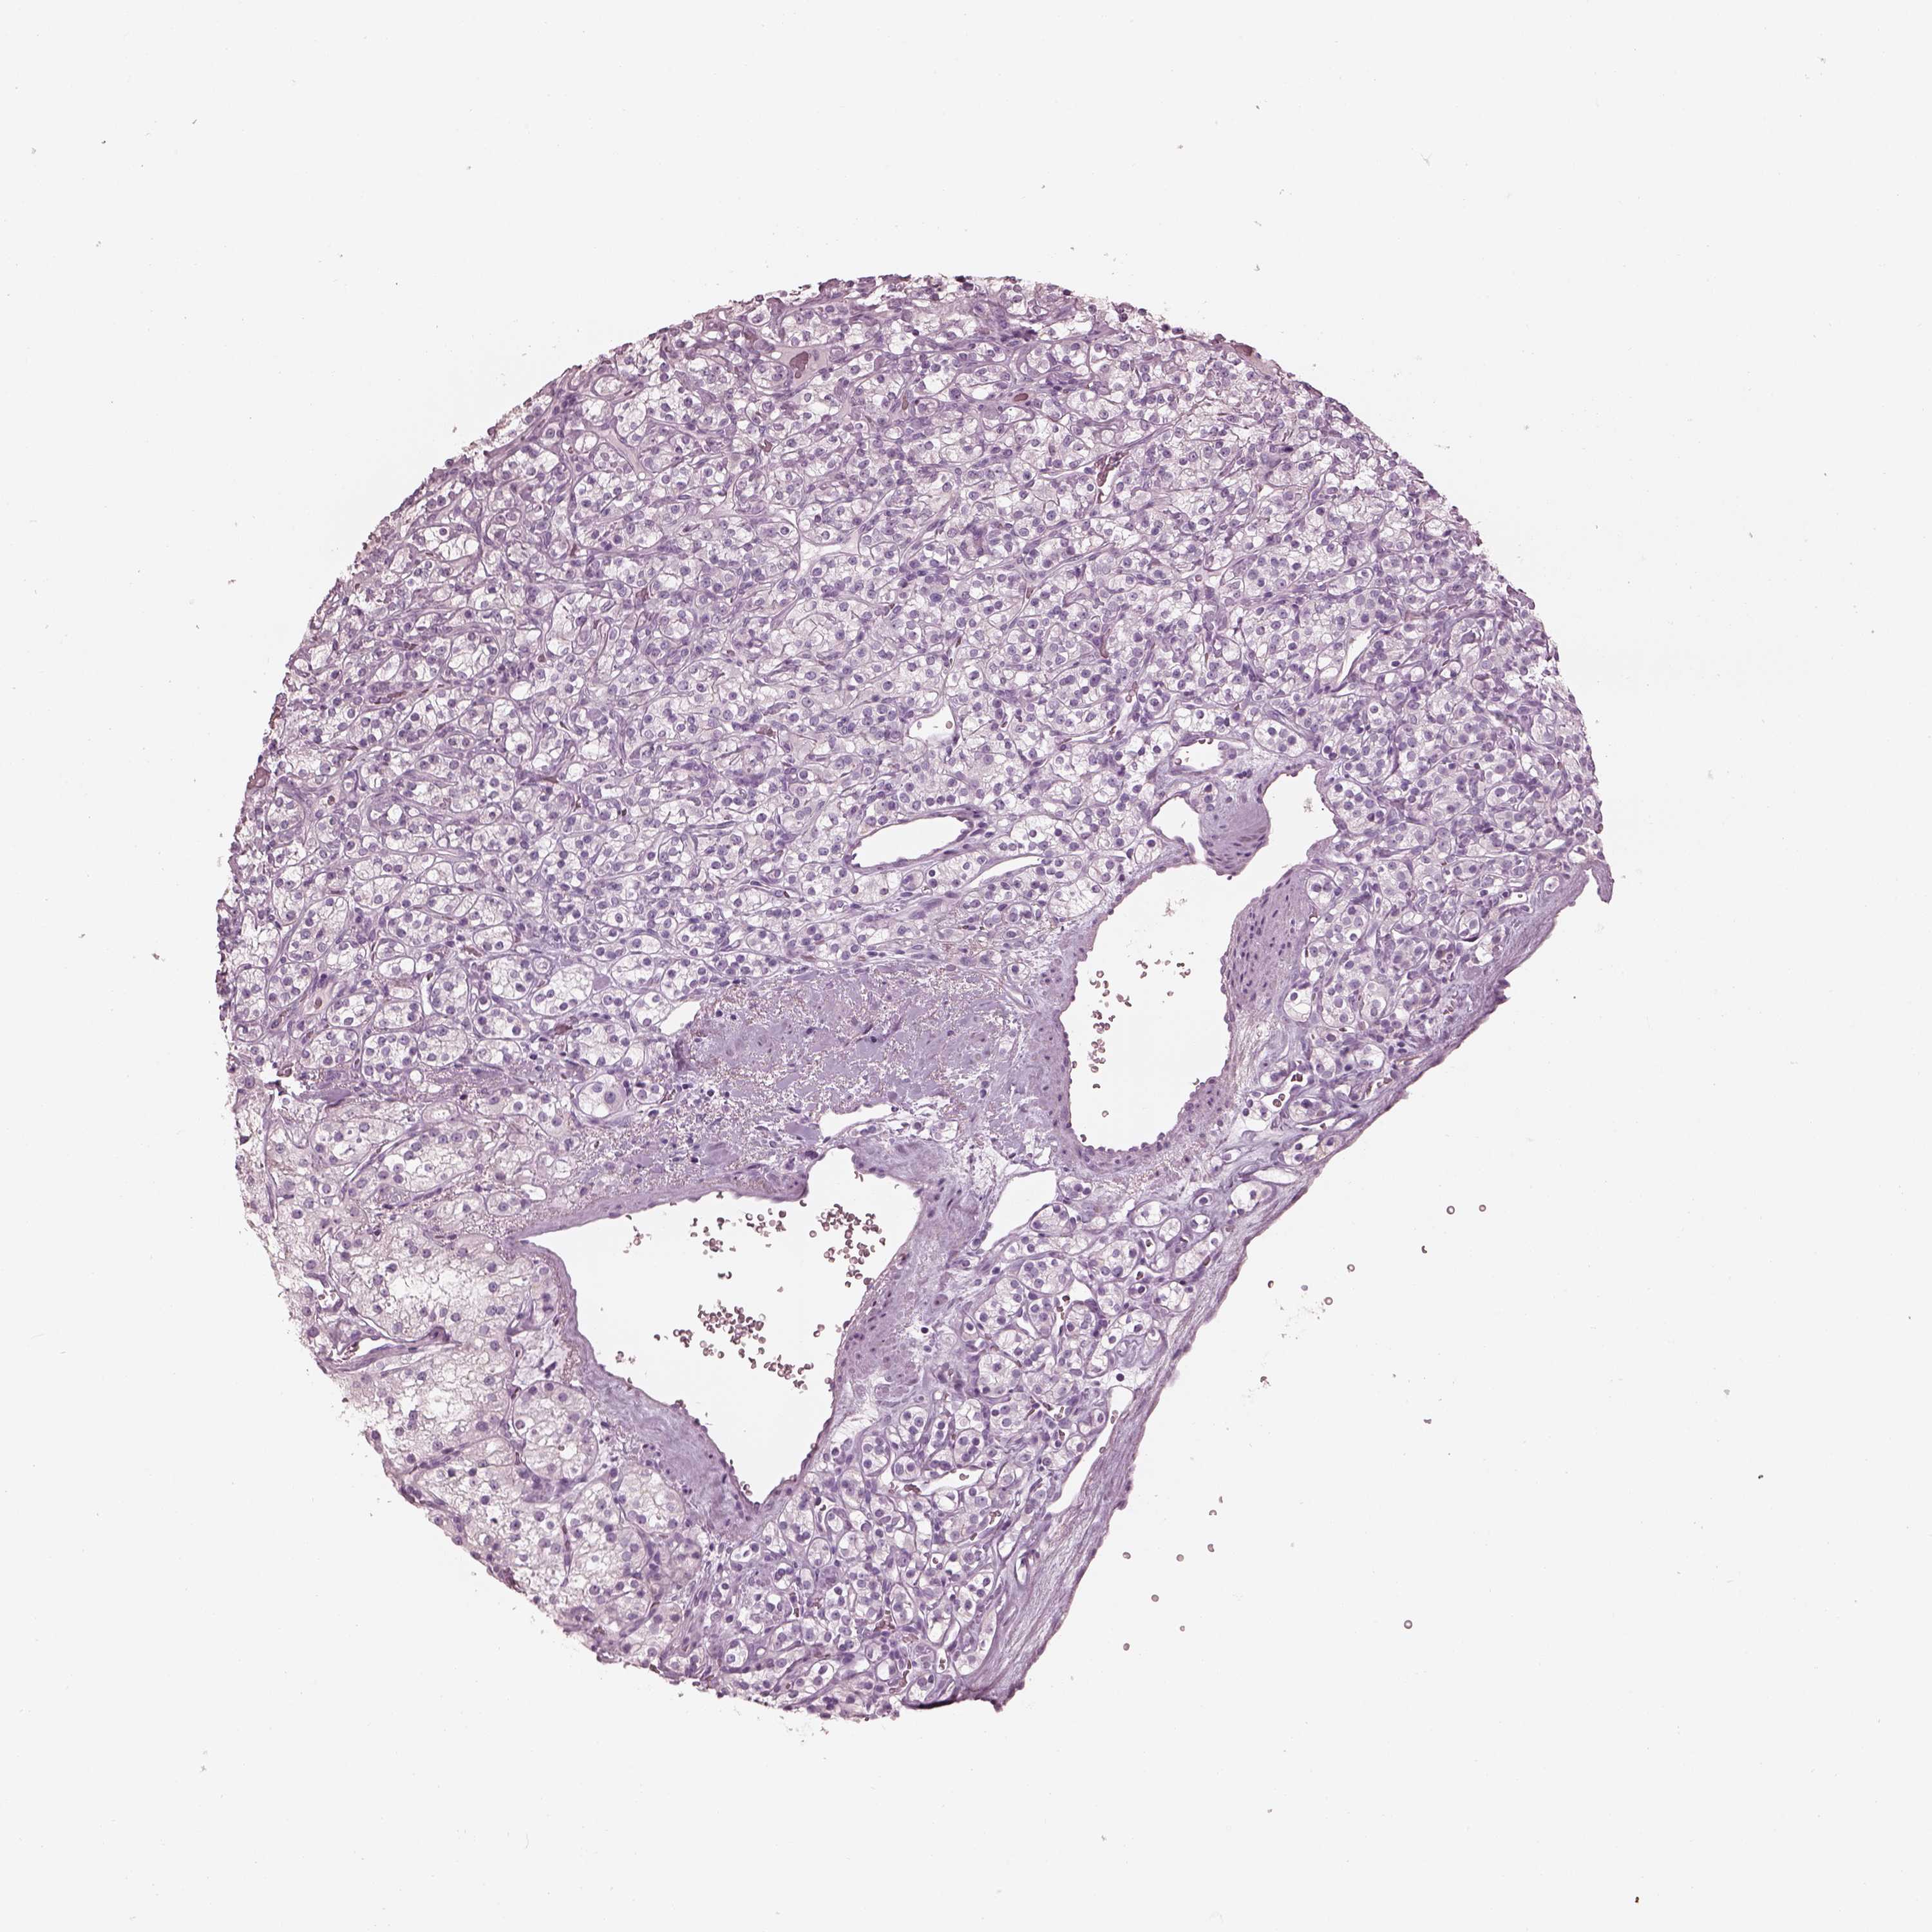

KIDNEY RENAL CLEAR CELL CARCINOMA (VALIDATION) - Interactive survival scatter ploti

The Survival Scatter plot shows the clinical status (i.e. dead or alive) for all individuals in the patient cohort, based on the same data that underlies the corresponding Kaplan-Meier plots. Patients that are alive at last time for follow-up are shown in blue and patients who have died during the study are shown in red.

The x-axis shows the expression levels (FPKM) of the investigated gene in the tumor tissue at the time of diagnosis. The y-axis shows the follow-up time after diagnosis (years). Both axes are complimented with kernel density curves demonstrating the data density over the axes. The top density plot shows the expression levels (FPKM) distribution among dead (red) and alive patients (blue). The right density plot shows the data density of the survived years of dead patients with high and low expression levels respectively, stratified using the cutoff indicated by the vertical dashed line through the Survival Scatter plot. This cutoff is automatically defined based on the FPKM cutoff that minimizes the p-score. The cutoff can be changed by dragging the vertical line or by entering a cutoff value in the square labeled "Current cut-off".

Under the Survival Scatter plot the p-score landscape (black curve; left axis) is shown together with dead median separation (red curve; right axis). Dead median separation is the difference in median mRNA expression between patients who have died with high and low expression, respectively. It is calculated as follows: median FPKM expression of dead patients with high expression - median FPKM expression of dead patients with low expression. This is intended to aid the user in visually exploring custom cutoffs and the associated p-scores and dead median separation.

Individual patient data is displayed and can be filtered by clicking on one or more of the category buttons on the top of the page. Categories describing expression level and patient information include: high, low, alive, dead, female, male and tumor stages. The scale of the x-axis can be toggled between linear and log-scale by clicking on the "x log" button. Mouse-over function shows TCGA ID, patient information and mRNA expression (FPKM) for each patient.

& Survival analysisi

Kaplan-Meier plots summarize results from analysis of correlation between mRNA expression level and patient survival. Patients were divided based on level of expression into one of the two groups "low" (under cut off) or "high" (over cut off). X-axis shows time for survival (years) and y-axis shows the probability of survival, where 1.0 corresponds to 100 percent.

Survival analysis data not available.

TCGA RNA samplesi

RNA-seq data is reported as average FPKM (number Fragments Per Kilobase of exon per Million reads), generated by the The Cancer Genome Atlas (TCGA) .

Normal distribution across the dataset is visualized with box plots, shown as median and 25th and 75th percentiles. Points are displayed as outliers if they are above or below 1.5 times the interquartile range. FPKM values of the individual samples are presented next to the box plot.

Average pTPM 0.0

Number of samples 100